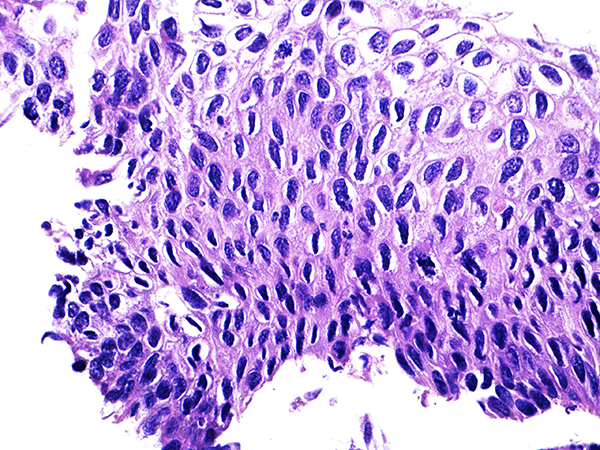

Case 1

Area 1 - Soft Bx CIN 2

40x - High Power